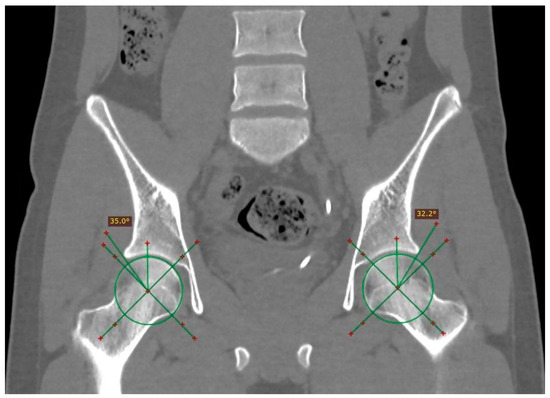

The distribution of pincer impingement with respect to laterality was 5.5% on the right side, 16.6% on the left side; while CAM impingement was present in 20% on the left side, 47% on the right, and 33% bilaterally (an example of bilateral FAI is shown in Figure 2).

Figure 2.

Computed tomography image showing bilateral pincer-type femoroacetabular impingement with coronal reconstruction and window for bone tissues, where acetabular over-coverage was identified with a center-right edge angle of 57.7° and a left angle of 47°. In addition, a stone was observed in the left ureter and a right double J catheter.